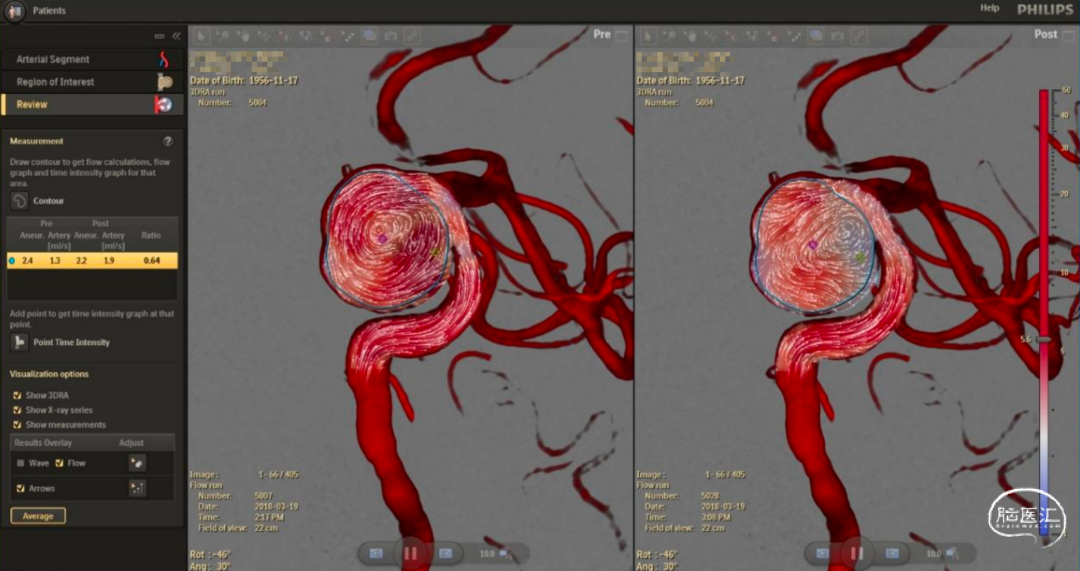

世界上第一个用于动脉瘤修复的功能性成像工具,扩展了神经介入的功能:

将载瘤动脉和动脉瘤血流类型可视化;

血流导向支架释放后,即刻量化动脉瘤内血流变化;

计算支架治疗前后的平均动脉瘤血流变化幅度比(MAFA比),评估动脉瘤内血流下降程度。

动脉瘤血流的对比变化以及可视性

可以针对选择感兴趣区域进行更多血流变化幅度进行评价,可以进行血栓形成的可能性指标。

右:AneurysmFlow功能可以可视化和量化动脉瘤内血流类型,评价血流转向支架放置前后的血流变化。